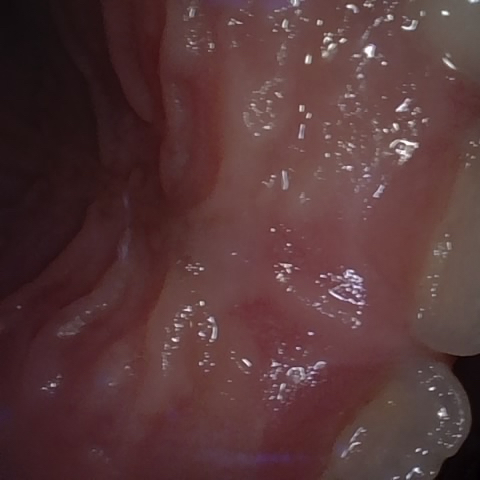

Incorrect Quality Level

The reference annotation for this image is

None

.

Please select the correct quality level.

Annotated as "Good"